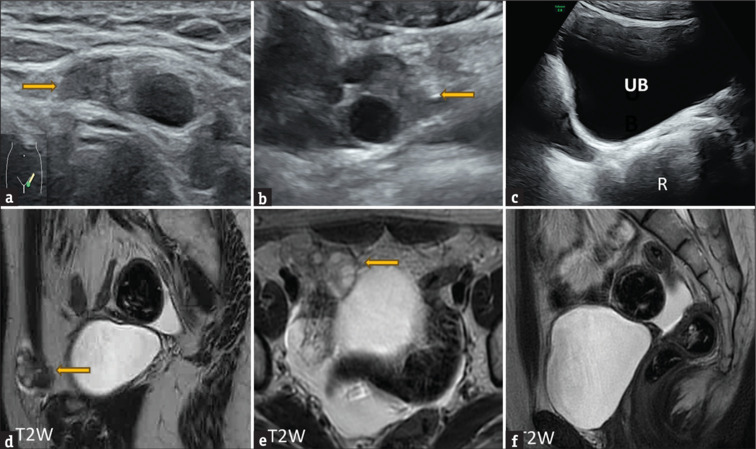

Inguinal hernia in females is an uncommon entity. While most patients present in infancy or early in childhood, only a few cases are diagnosed in adulthood. Most cases of inguinal hernia have small bowel or omentum as its content. Herniation of the ovary or fallopian tube is rare. In our case, an 18-year-old female presented to the outpatient department with unilateral inguinal swelling, which on imaging was found to be ovarian inguinal herniation. This prompted further evaluation. There was an associated absence of the uterus and left kidney, and congenital block vertebrae involving the cervical spine. On probing it was found that she had primary amenorrhoea with normal secondary sexual characteristics. All the findings led to the diagnosis of Mayer Rokitansky Kuster Hauser type II or Mullerian duct aplasia renal agenesis cervicothoracic somite dysplasia (MURCS) with unilateral inguinal ovarian herniation. Mullerian duct aplasia renal agenesis cervicothoracic somite dysplasia (MURCS) present a challenge as they require a multidisciplinary team including gynaecologist, surgeon and psychologist to preserve the ovarian function and help the patient counsel regarding the reproductive outcome and wade through the associated emotional stress.